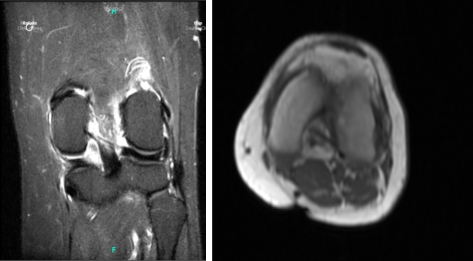

Patient returned to our office a week after the initial visit. Presented bilateral X-rays. Left knee demonstrates small full-thickness cartilage defects of the medial with inferior aspect of the lateral patellar facets with underlying patchy subchondral bone marrow edema.

Small partial-thickness cartilage defects on the medial trochlear facet. Small partial thickness cartilage loss central aspect of the medial femoral condyle with underlying small faint subchondral bone marrow edema. Small joint effusion and intact cruciate and collateral ligaments.

Her MRI right knee showed impression as follows: full-thickness cartilage defect inferior aspect of the lateral patellar facet and small full-thickness cartilage fissures of the medial patellar facet with underlying subchondral bone marrow edema.

Small full-thickness cartilage fissure of the medial trochlear facet with underlying small subchondral edema. Small full-thickness cartilage defects central aspect of the medial femoral condyle with underlying small subchondral bone marrow edema. Small to moderate joint effusion. Trace popliteal cyst.